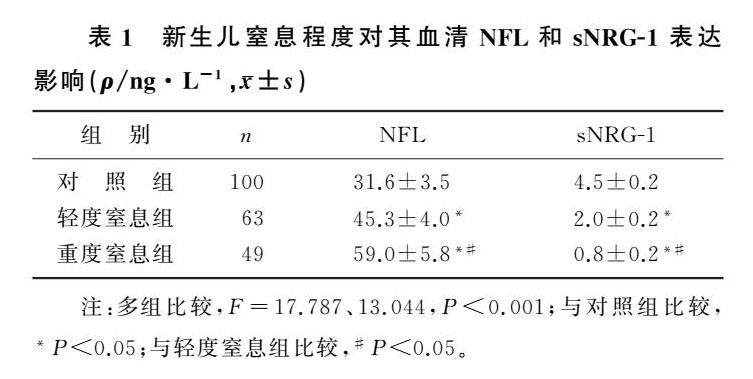

论著 | 窒息性脑损伤新生儿血清NFL和sNRG1检测及意义

论著 | 窒息性脑损伤新生儿血清NFL和sNRG1检测及意义